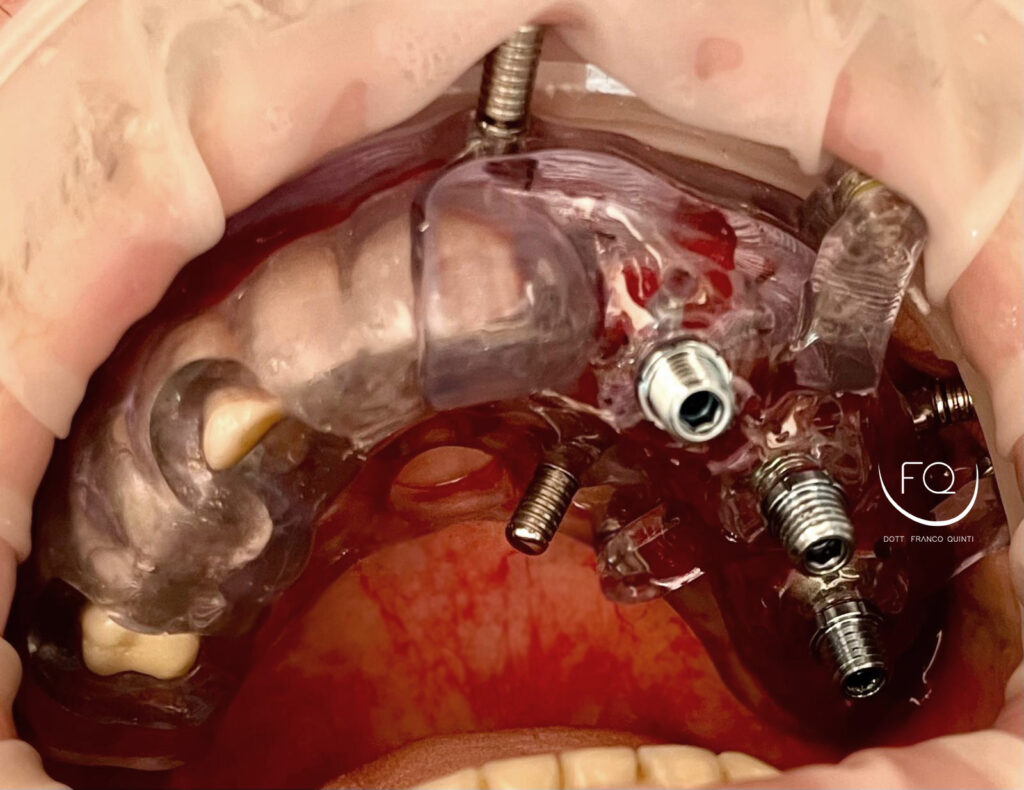

Questa settimana vi presento un caso di chirurgia computer guidata monolaterale, eseguito con l’utilizzo di una dima scomponibile ad appoggio dentale.

Durante l’intervento sono stati inseriti tre impianti PRAMA 3.8 × 11.5 di Sweden & Martina, successivamente sottoposti a carico immediato.